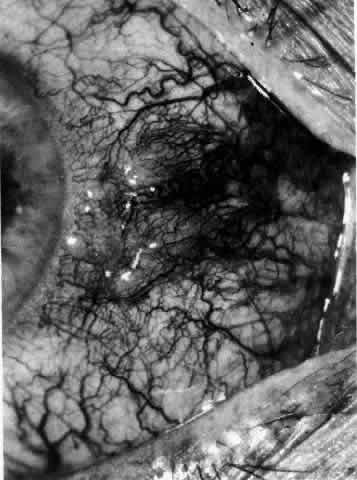

not be performed. Scleritis usually affects the anterior segment of the eye, possibly because

this is the area with the best blood supply, but with sluggish flow

through the vessels (Fig. 19). The sclera is thickened and roughened in the affected area, which appears

can be mistaken for malignant melanoma.  Fig. 19. Anterior necrotizing scleritis. The eye was removed because of loss of

vision and intractable pain. No form of steroid was given to this patient

because of a severe Pseudomonas infection of the chest. (Courtesy of Professor N. Ashton) Fig. 19. Anterior necrotizing scleritis. The eye was removed because of loss of

vision and intractable pain. No form of steroid was given to this patient

because of a severe Pseudomonas infection of the chest. (Courtesy of Professor N. Ashton)